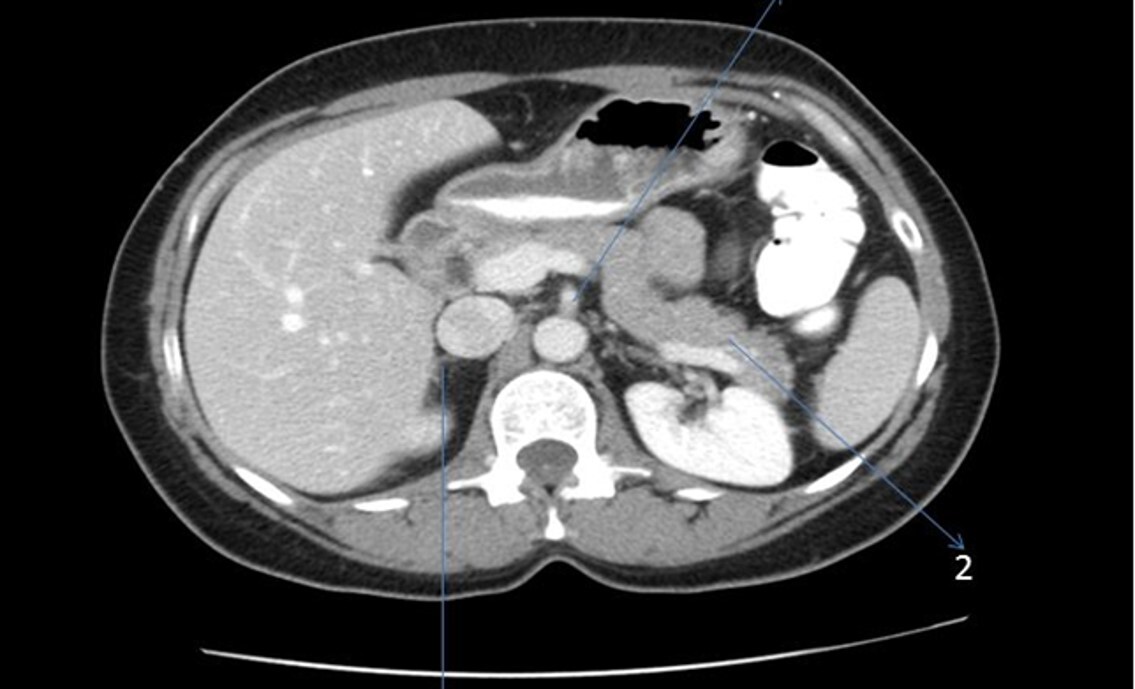

Q

What phase of contrast enhancement is seen in the abdomen CT image?

a Non-contrast

b. Bolus

c. Non-equilibrium

d. Equilibrium

A

Bolus